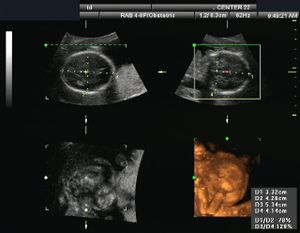

-

صورة ثلاثية الأبعاد لجنين عمره 29 أسبوع.